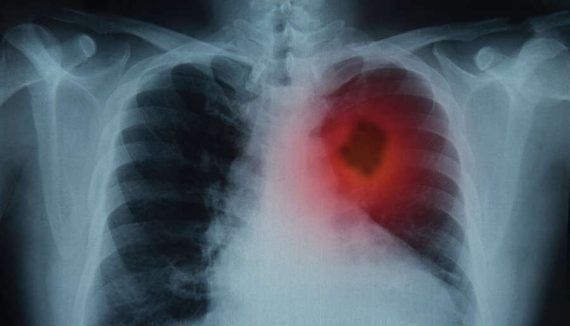

Για τη διάγνωση του καρκίνου του πνεύμονα θα πρέπει αρχικά να κάνετε μία ακτινογραφία στον θώρακα. Έπειτα θα ακολουθήσει μία αξονική τομογραφία θώρακος και στη συνέχεια μία βιοψία. Ενδέχεται να χρειαστούν κι άλλες εξετάσεις όπως είναι το ΠΕΤ – Σκαν που ανιχνεύει αν ο καρκίνος έχει κάνει μετάσταση και σε απομακρυσμένα όργανα ή ιστούς ή ακόμη και μαγνητική, αφού η πιο συχνή μετάσταση καρκίνου του πνεύμονα είναι στον εγκέφαλο.